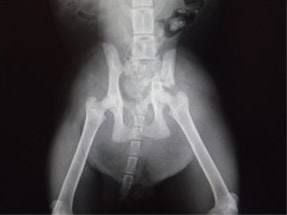

骨盤骨折 : 症例1 | 症例2 | 症例3 | 症例4